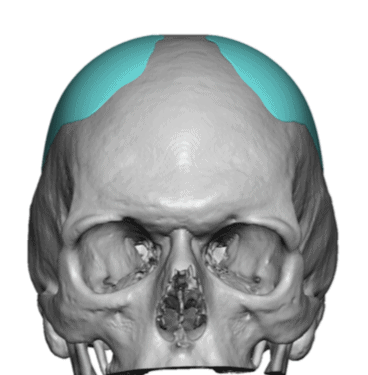

Desire for a higher and more prominent crown of the skull.

Crown of skull augmentation using a custom skull implant.

Desire for a higher and more prominent crown of the skull.

Crown of skull augmentation using a custom skull implant.